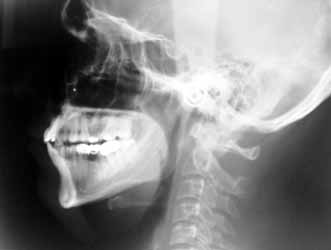

OPG & Cephalogram

What

is OPG?

OPG stands for Orthopantomography. It is a special method for obtaining

radiographs of the teeth-bearing jaws, both upper and lower.

How is it different from regular X-ray machines?

A regular X-ray machine cannot take detailed pictures of the jaw-bones. An OPG

machine is specially constructed so that it rotates around the jaw-bones, thus

giving us an extremely good idea about the structure of the jaw bones. Yes,

x-rays are used, but the method is totally different.

In what situations are they needed?

OPG x-rays are usually asked for by dentists, whether they be general dentists,

orthodontists, oral surgeons or prosthodontists/implantologists. Because OPGs

give a bird-eye view of the teeth and the adjacent bones, they are useful in a

wide-variety of conditions including infections, tumors, congenital

abnormalities, pre-implant evaluation and trauma.

is a cephalogram?

It is an x-ray of the face, obtained so that accurate measurements of the face

can be performed.

What is its use?

Oral surgeons, orthodontists and prosthodontists need cephalograms prior to

planning surgeries and teeth manipulation.

How much time does it take?

On an average, 20 minutes.

How much does it cost?

Rs 300